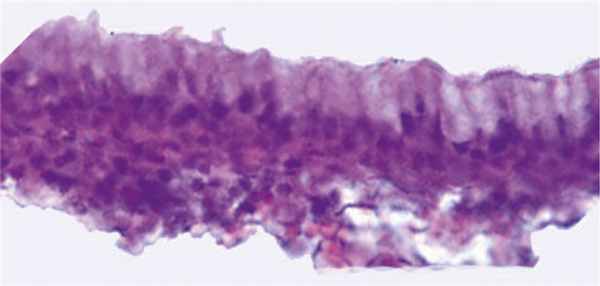

Заключение патогистологического исследования оболочки кисты: в срезах препарата оболочка кисты Торнвальдта, выстланная изнутри призматическими клетками (рис. 2). Элементы хронического воспалительного процесса.

Рис. 2. Оболочка кисты Торнвальдта. Внутренняя стенка выстлана призматическими клетками. Fig. 2. The e nvelope of Thornwaldt’s cyst. The inner wall is lined with prismatic cells.Окраска гематоксилином и эозином. Ув. 400. Staining with hematoxylin and eosin, x400.